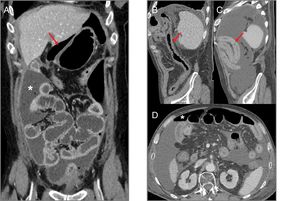

Figure 8.(A and B) Patient with stage IV squamous cell carcinoma of the lung, on third-line treatment with nivolumab, presenting with diarrhoea and a febrile episode. Computed tomography (CT) shows a slight diffuse wall thickening with increased enhancement of the mucosa of the colon (arrows), which extends from the transverse colon to the rectum, suggestive of colitis. (C and D) Patient with stage IV renal carcinoma due to pulmonary involvement, being treated in a clinical trial with combined nivolumab and ipilimumab therapy. The patient had a history of very intense headache for several days, without pyrexia and with normal brain CT. The magnetic resonance imaging (MRI) volumetric interpolated breath-hold examination (VIBE) (C) and T1 sequences with contrast (D) show the pituitary gland to be enlarged in relation to the age of the patient (craniocaudal diameter 9mm), with a convex-shaped superior margin and homogeneous enhancement which, in the clinical context of the patient is suggestive of immune checkpoint inhibitor-induced hypophysitis.

Hypophysitis: hypophysitis has primarily been associated with treatment with ipilimumab. It tends to occur nine weeks after starting treatment and has an incidence of 2–4%.31 Initial symptoms are headache and fatigue, followed by hypothyroidism, hypogonadism and hypocortisolism.30

Araujo et al.37 reviewed the cases of 57 patients with ipilimumab-related hypophysitis and identified abnormal imaging findings in 77%. Typical imaging findings are a symmetrical increase in the size of the pituitary gland, which acquires a convex shape, with thickening of the stalk or infundibulum, and homogeneous enhancement after the administration of contrast (Fig. 8C and D). After corticosteroid treatment, follow-up images may show a decrease in pituitary size, a change in shape from convex to concave, and even in extreme cases an empty sella turcica. The majority of patients have no recovery of pituitary function.37,38